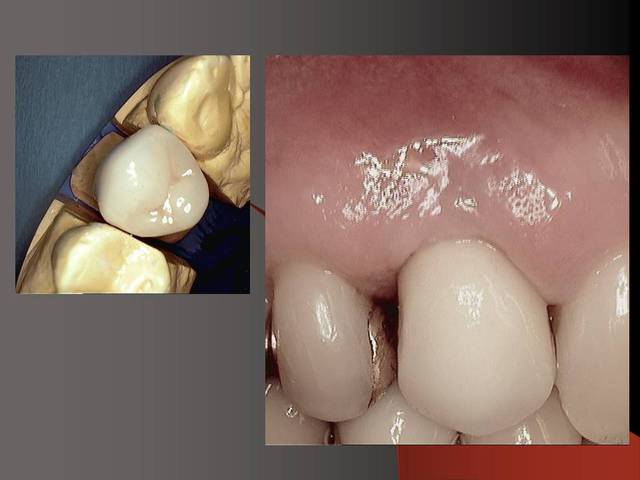

Photos d'un cas d'extraction implantation immédiate, stabilité primaire (de mémoire) assez élevée.. 60/70 N ..démontage du gingiva clips et du shuttle, pilier serré 40N, couronne procera

Merci pour le cas, bien fait. Belle présentation photo.

Assez classique d'un implant 2 pièces.

Le contour gingival est net, belle guérison, c'est à combien de semaine ?

Je vois un peu de ciment sur la radio finale, attention, c'est pas bien pour les tissus.

Oui je sais pour le ciment... j'utilise d'ailleur ce cas et cette radio dans une présentation pour mettre en garde sur le risque au moment du scellement de voir du ciment fuser sous la limite prothétique vers la col de l'implant..galère à éliminer...Personnellement je préfere plutot utiliser des piliers à usiner (maintenant disponibles voir shop online pour photos) au lieu des strandarts meme si il y a deux hauteurs/col implantaire en 1 et 3mm aujourd,hui disponibles..A l'époque de ce cas il n'y avait que les 1 mm et la limite est un "poil" trop profonde.

La pose de la couron nec'est faite 8 semaines apres l'extraction implantation immédiate, la particularité de ce systeme permet de ne pas démonter le shuttle ni la gingivaclip pour l'empreinte..je pense que ca aide bien à la qualité gingivale...radio controle ci jointe